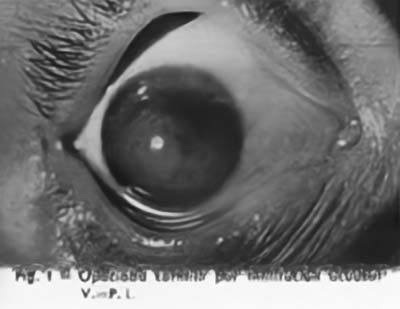

La Cirugía Laminar Refractiva conocida hoy con los nombres de LASIK, PRK, LASEK, se inició a mediados del siglo XX, cuando tratando de solucionar los problemas de visión de los pacientes con Queratocono un oftalmólogo el Dr José I. Barraquer Moner, pudo observar la gran disminución del defecto miópico que padecían, despues realizar sobre los grandes conos un injerto de córnea laminar de 12 mm de diámetro. La aplanación subsecuente de la córnea generaba el cambio refractivo

Inició entonces la observación clínica de los cambios refractivos que ocurrían en las diferentes patologías corneales resultantes de la cicatrices quirúrgicas o accidentales, asi como de las ametropías que generalmente acompañan los valores extremos de la curva corneal ( hipermetropía en los casos de córnea plana, miopía en los casos de córneas muy curvas), confirmando la posibilidad de corregir los defectos de la refracción por modificación del radio de la curvatura corneal.

Esto lo llevó a modificar manualmente la forma o el espesor del tejido donante en las queratoplastias laminares pudiendo comprobar la veracidad de su hipótesis.